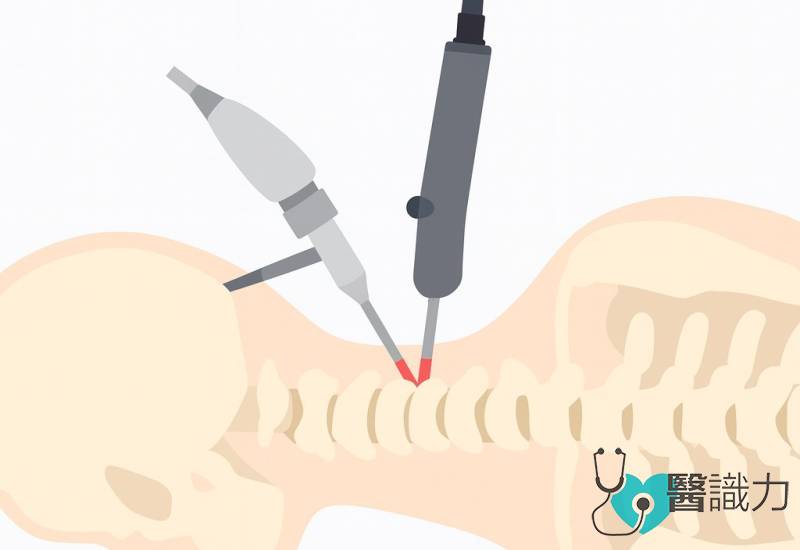

我们第一时间为他进行全身检查和扫描,发现他的第五节和第六节颈椎椎板骨折并移位往前,压迫脊髓,神经线因而受压,造成右侧臂丛神经损伤(right brachial plexus injury),头颈无法转动,右侧手脚麻木无力,脊椎也有不稳定的迹象。

像艾文这样的脊椎伤者,发生意外后切忌随意移动,搬运时必须固定在长背板或担架上,让头、颈和身体呈一直线,减轻对脊髓的压力,同时套上颈圈,固定头部和颈部,最重要的原则是保持颈椎和脊柱稳定,绝对不能让颈部和身体弯曲或晃动。

由于伤势严重,艾文必须马上接受颈椎前后稳固定型手术,术后再努力复健,希望可以慢慢恢复健康。